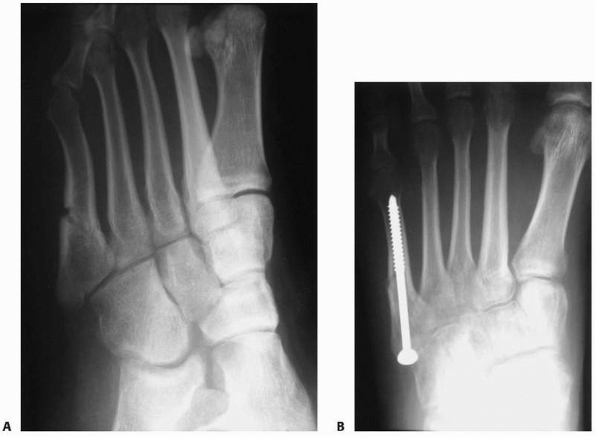

symptoms will have radiographic evidence of delayed union or nonunion.

Delayed unions demonstrate a wider fracture completely through the

medial and lateral cortices with some medullary sclerosis (Fig. 19-6).

A very wide gap with periosteal new bone formation and complete

medullary sclerosis characterizes the appearance of established

nonunions.183,185 Delayed unions may heal with prolonged non-weight-bearing cast immobilization, but functional recovery often requires 6 months.185,195

grafting. Others propose a sliding bone graft53 or compression screw fixation56,113,147 (Fig. 19-6). For those averse to surgery, electrical stimulation has been shown to be effective.90

FIGURE 19-6 Middle-aged recreational runner with several-month history of worsening activity-related lateral foot pain. A.

Intermediate delayed union fifth metatarsal stress fracture with a complete fracture, some widening of the cortical gap, and moderate medullary sclerosis. B. Radiographic appearance 3 months following medullary drilling, bone grafting, compression screw stabilization, and initial period of non-weight bearing. |